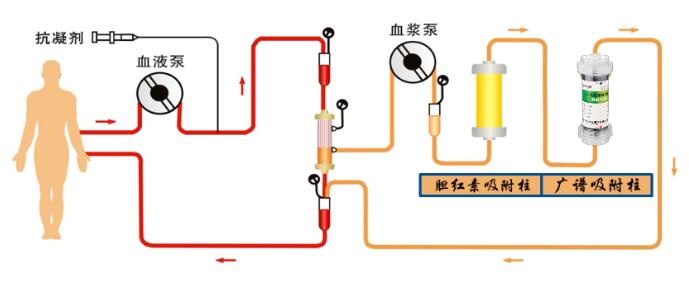

希尔康RC灌流器在双重血浆吸附联合半量血浆置换治疗中的应用

2023-09-21

了解更多